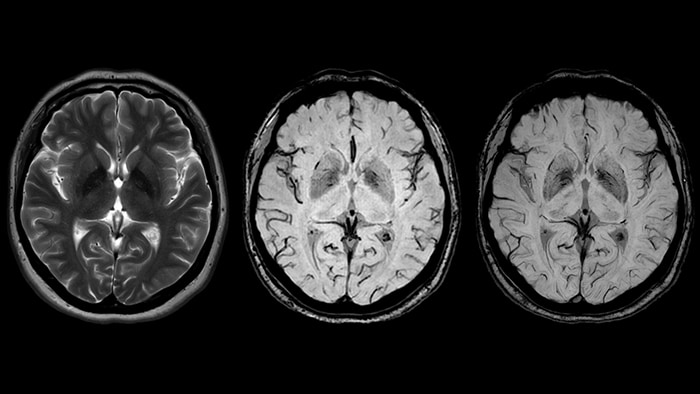

Хроническая ишемия головного мозга и лейкоареоз: симптомы и лечение